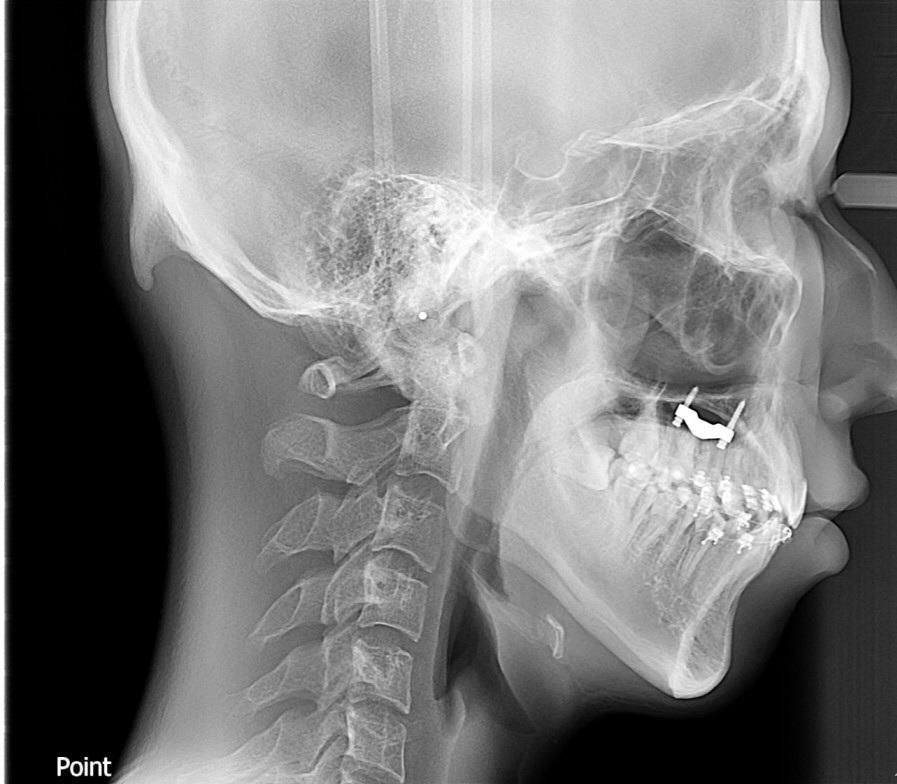

marpe을 1년동안 게속돌려서 다른사람들보다 marpe장치를 훨씬많이돌렸는데 귀에서 눈까지거리(얼굴앞뒤뼈가) 교정전보다 훨씬 커진것같은데 엑스레이상에서도 훨씬 커지게 나왔는데 확인부탁드립니다 귀에서 눈까지거리

• 2번 째 사진

간접적인 영향이지 직접적으로 영향을 미치지 않습니다. 또한 소아 청소년기에 이러한 변화가 나타날 가능성이 있으며 성인기에는 변화 가능성이 적다고 보시면 됩니다. 또한 다음 사진은 정확히 같은 지점을 계측하지 않았으므로 해당 사진만으로 판단할 수 없습니다.

전후 셉 사진이 있으니 계측하여 비교는 가능합니다

동일조건(머리 자세, 기계 세팅값)하에 찍어야 하고 두 사진을 중첩하여 최적중첩법, 안정골구조물 중첩법 등을 이용하면 하악골의 변화 측정가능합니다 병원에 해달라고 요청하세요 아쉽지만 아하 온라인상에선 못합니다